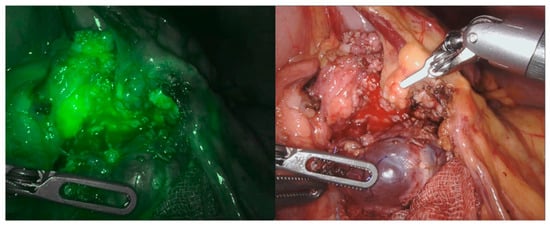

5. Near-Infrared Fluorescence and Robotic-Assisted Abdominal Surgery

- Esposito, C.; Settimi, A.; Del Conte, F.; Cerulo, M.; Coppola, V.; Farina, A.; Crocetto, F.; Ricciardi, E.; Esposito, G.; Escolino, M. Image-Guided Pediatric Surgery Using Indocyanine Green (ICG) Fluorescence in Laparoscopic and Robotic Surgery. Front. Pediatr. 2020, 8, 314. [Google Scholar] [CrossRef] [PubMed]

- Spinoglio, G.; Bertani, E.; Borin, S.; Piccioli, A.; Petz, W. Green indocyanine fluorescence in robotic abdominal surgery. Updates Surg. 2018, 70, 375–379. [Google Scholar] [CrossRef] [PubMed]

- Boni, L.; David, G.; Mangano, A.; Dionigi, G.; Rausei, S.; Spampatti, S.; Cassinotti, E.; Fingerhut, A. Clinical applications of indocyanine green (ICG) enhanced fluorescence in laparoscopic surgery. Surg. Endosc. 2015, 29, 2046–2055. [Google Scholar] [CrossRef] [Green Version]